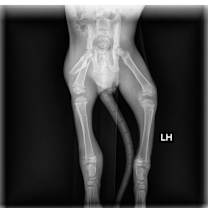

Greenlee came to us with a badly broken rear right leg. The vet originally thought the only option would be to amputate the leg. Fortunately, with lots of rest, the leg healed (it is not healed "normally"), but he is able to use the leg and behave like a totally normal kitten. You have to watch him closely to see the slight limp.